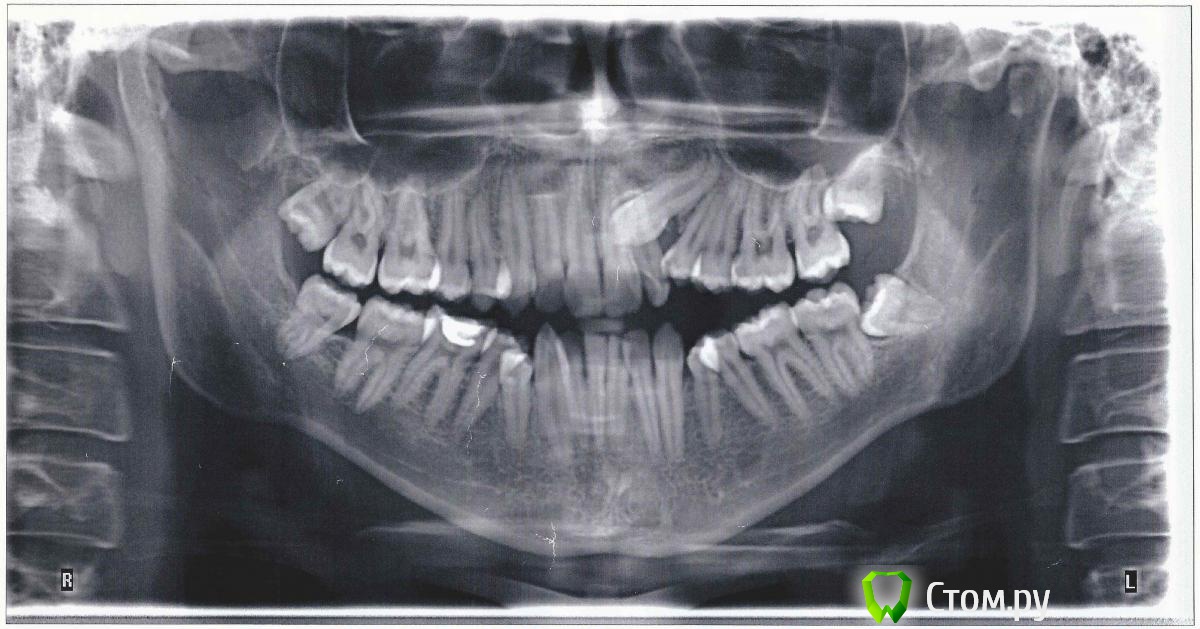

Здравствуйте! У меня очень большая скученность зубов. Ходил к нескольким ортодонтам в своём городе, они говорят, что необходимо удалить все 4-ки и только после этого ставить брекеты.

два других доктора говорили, что достаточно удалить только нижнюю левую четвёрку.

Правый клык, говорят, что можно вытянуть и поставить на место.

Я хочу удалить верхние восьмёрки и нижнюю правую восьмёрку, поможет ли это в итоге сдвинуть остальные зубы особенно в правой части верхней челюсти за счёт освобождения места от восьмёрки, или коренные зубы уже никак не сдвинуть?

Какие можете дать рекомендации судя по снимку? Спасибо.

По снимку могу сказать только,что потребуется удаление всех 8-ок,независимо будет удаление премоляров (в Вашем случае Вы ведете речь о 4ках) или нет в плане лечения.